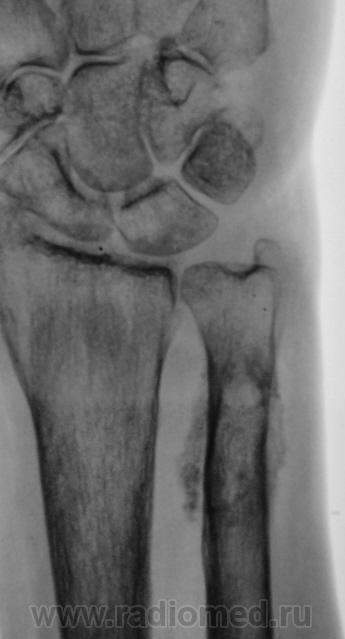

патологический перелом н\3 предплечья. Действительно без боковой проекции просто никуда!

Консолидированный нормальный перелом ))))))))))))))))) Просто гематома обызвествилась.

Что за причины быть ему патологическим? нормальный перелом, удовлетворительная консолидация

что имеется полость в проекции диафиза локтевой кости.

"Полость" - это игра теней.

Согласен, что перелом не патологический, скорее "геронтологический".